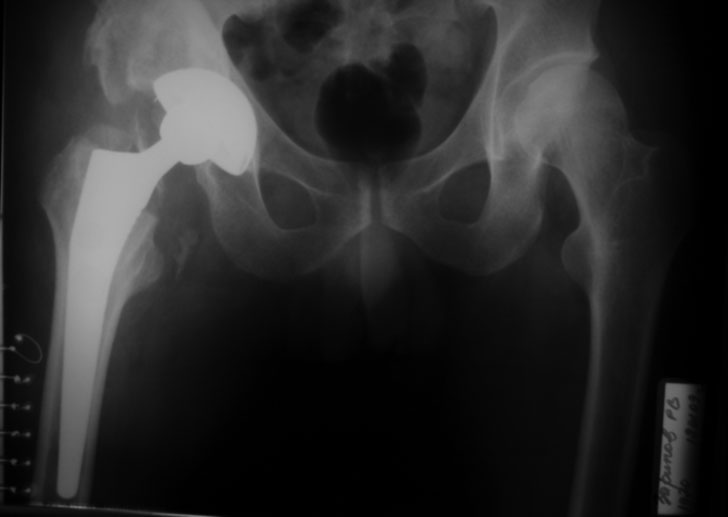

тема обсуждалась http://weborto.net/forum/1226122957/index_html#1226722831, низведение бедра - 3 нед, артроплстика Corail-Duraloc? ранний п/о период, пока спокойно.

Имя     : до.jpg

Url     : http://weborto.net:8080/pipermail/ortho/attachments/20090119/0ccb8dff/attachment-0004.jpg